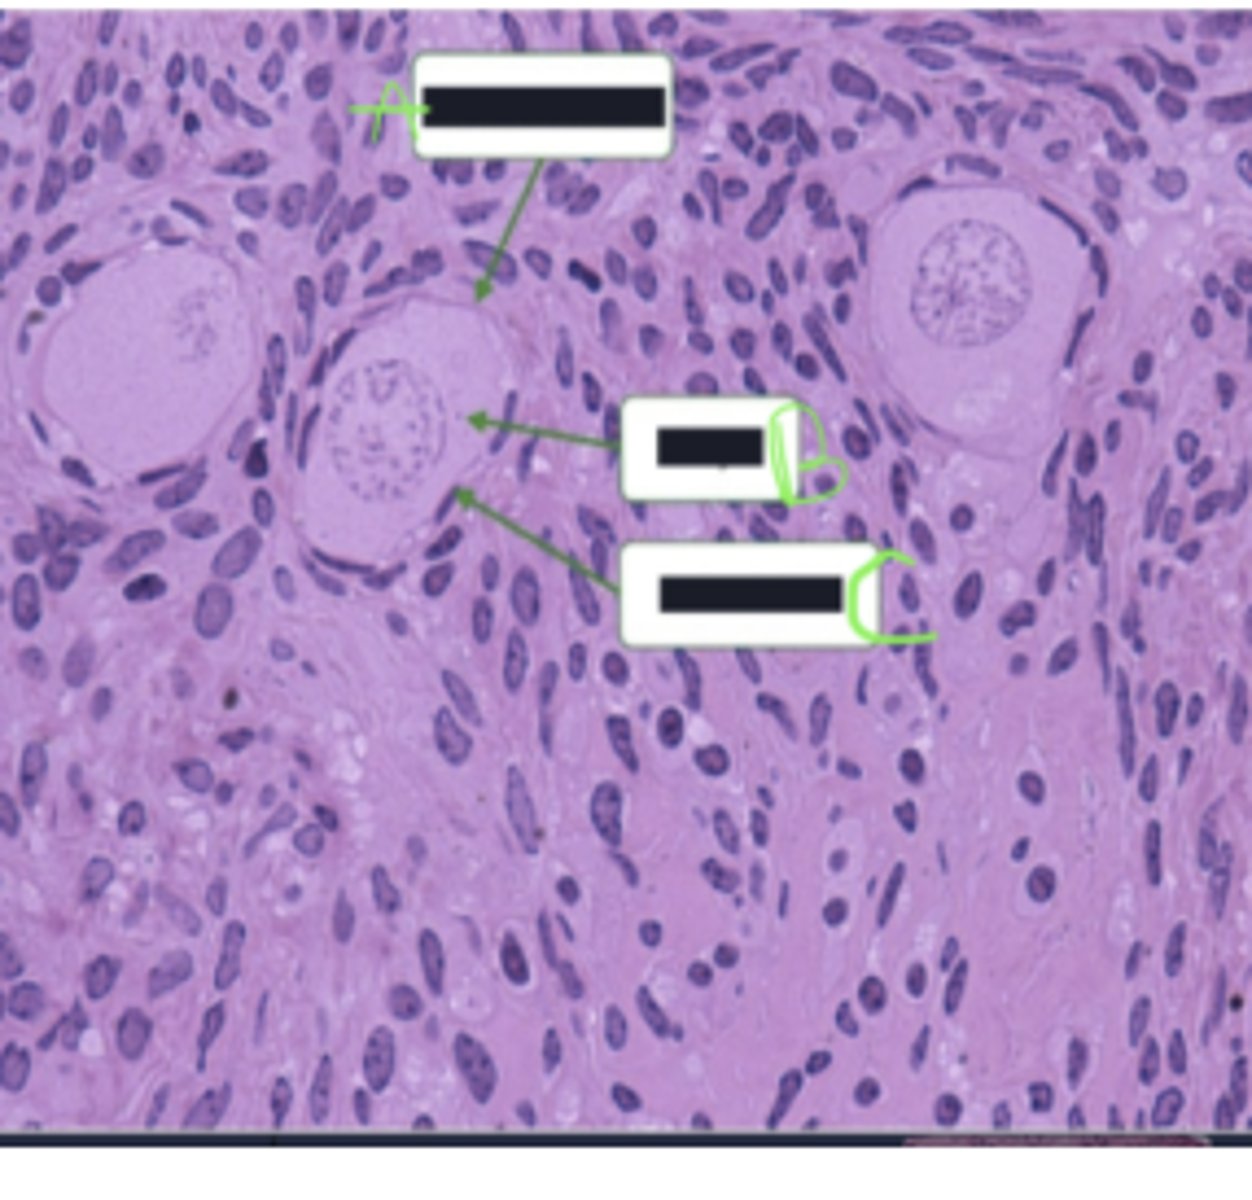

green arrow = centroacinar cell

seminiferous tubules